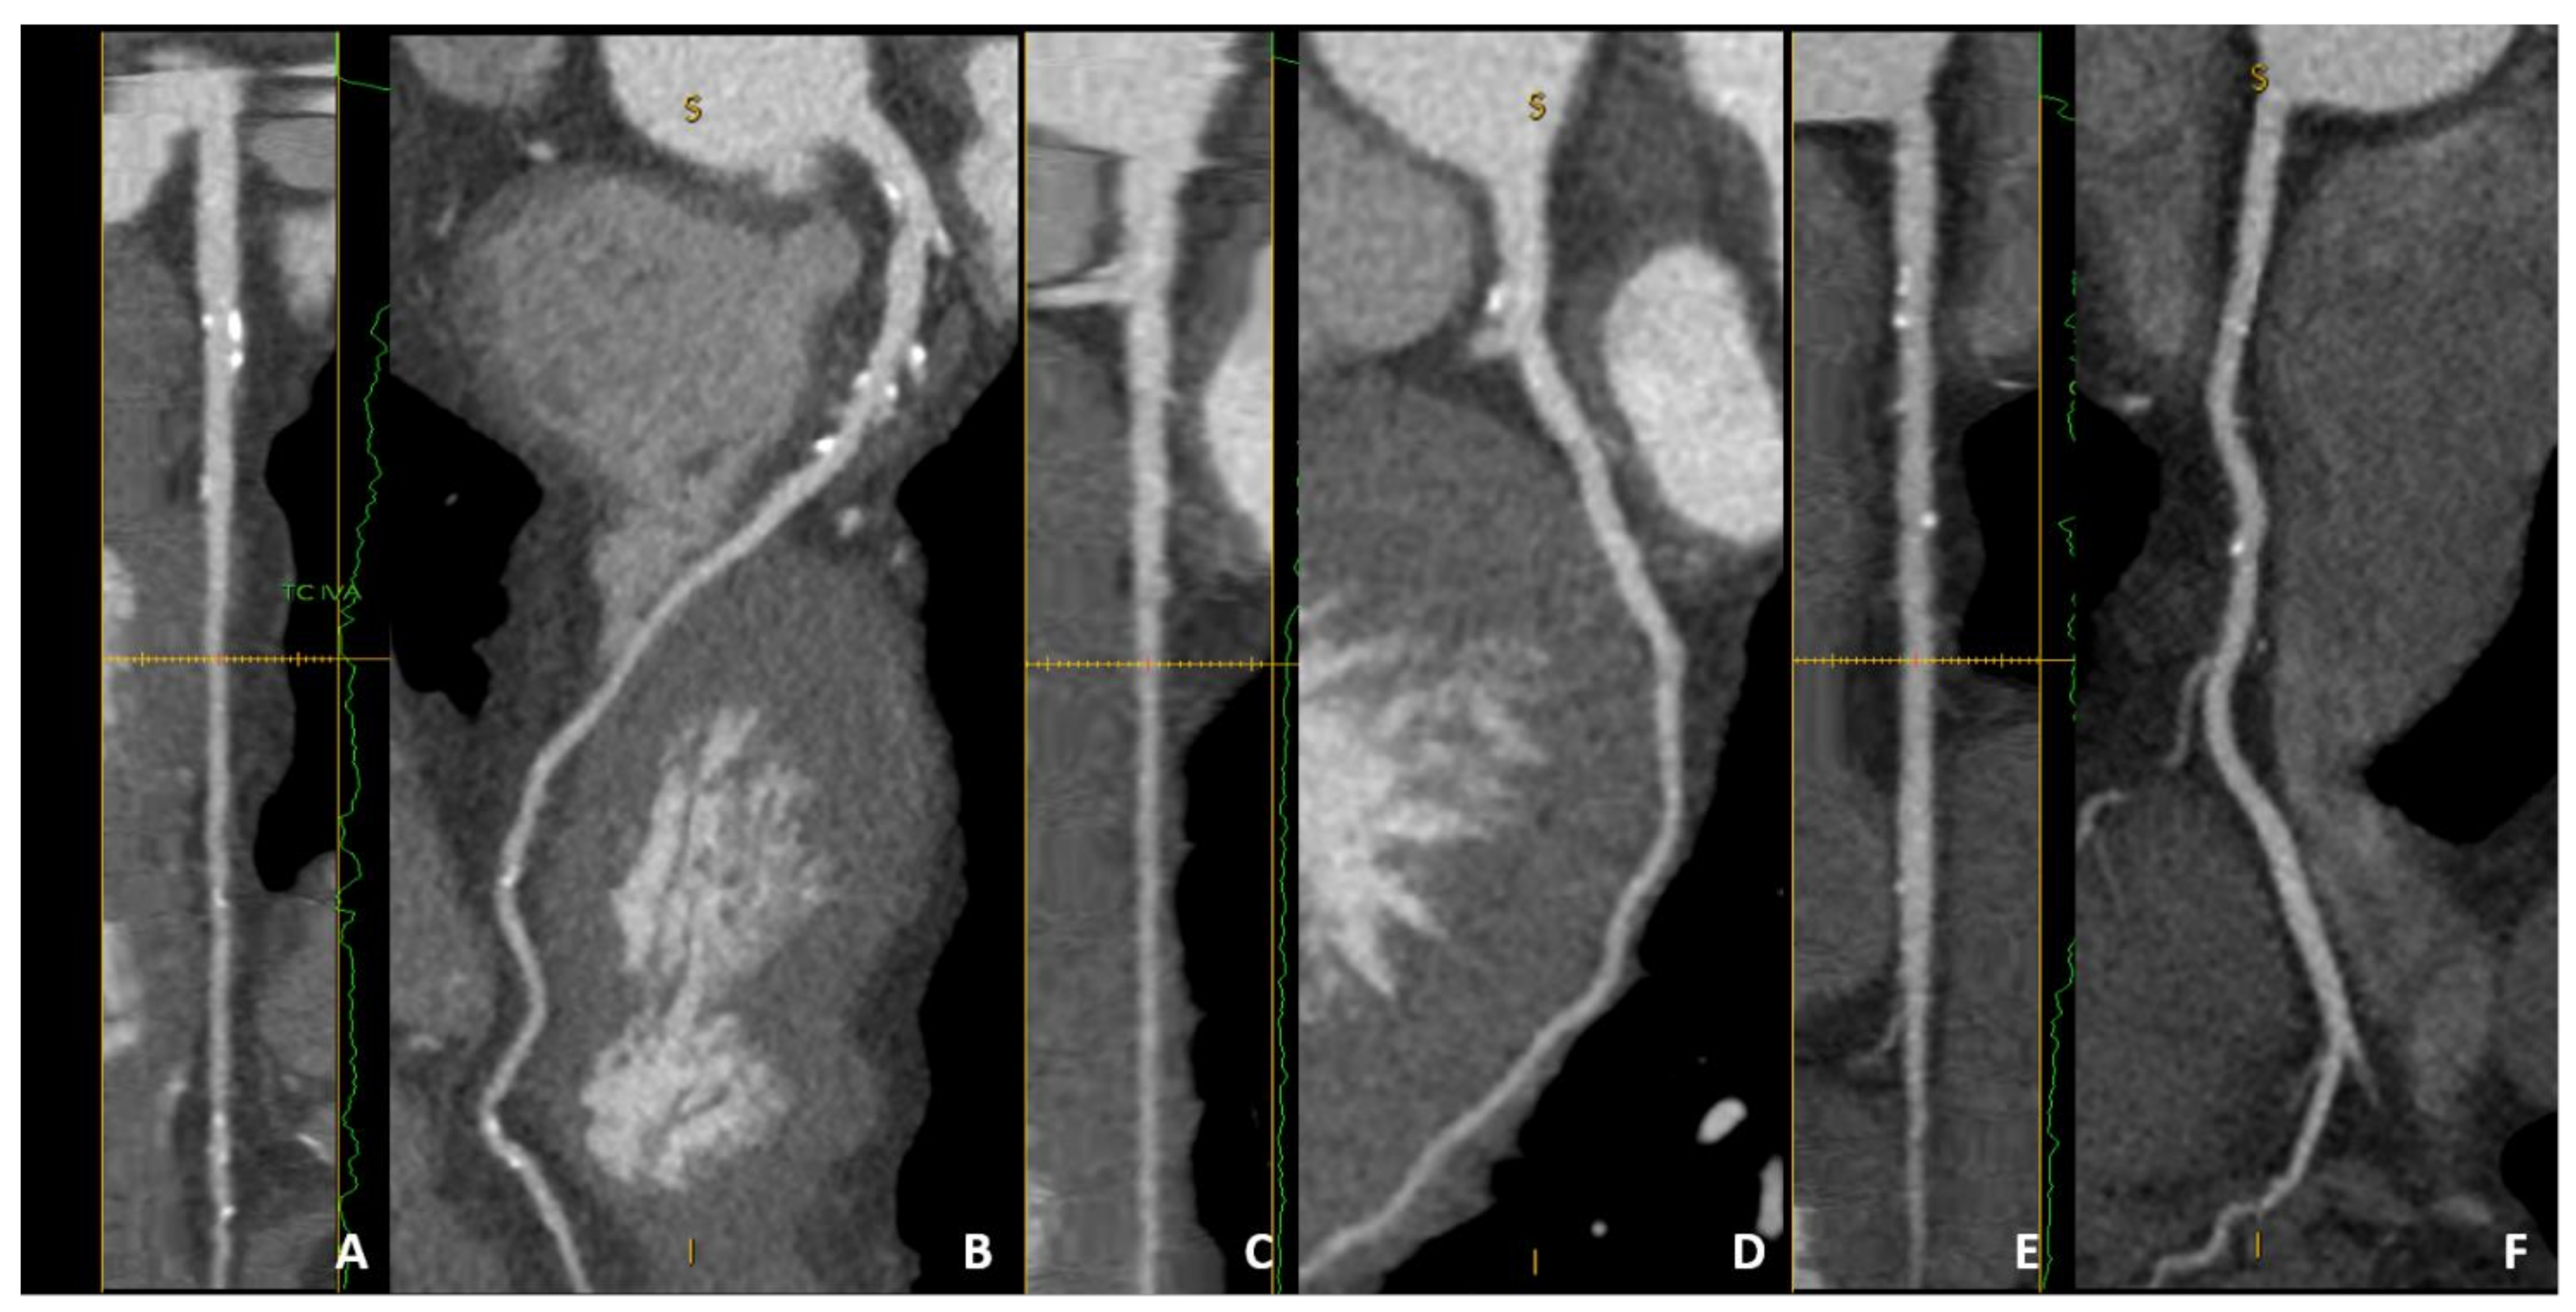

| Remodeling index (RI) | Ratio between lesion plaque area (red circle) and reference lumen area (blue circle). Positive remodeling is defined as RI > 1.1. | ![]() |

| Low-attenuation plaque (LAP) | Presence of any voxel < 30 HU in a coronary plaque. | ![]() |

| Plaque burden (PB) | Derived by the following formula: (lesion plaque area (red circle)—lesion lumen area (blue circle))/lesion plaque area (red circle). | ![]() |

| Napkin-ring sign (NRS) | Presence of rim-like thin enhancement (no more than 130 HU) distributed along the outer contour of the vessel and surrounding a fibro-lipidic plaque. | ![]() |

| Small spotty calcifications (SC) | Any discrete calcification ≤ 3 mm in length and occupying ≤ 90° arc when viewed on short axis. | ![]() |